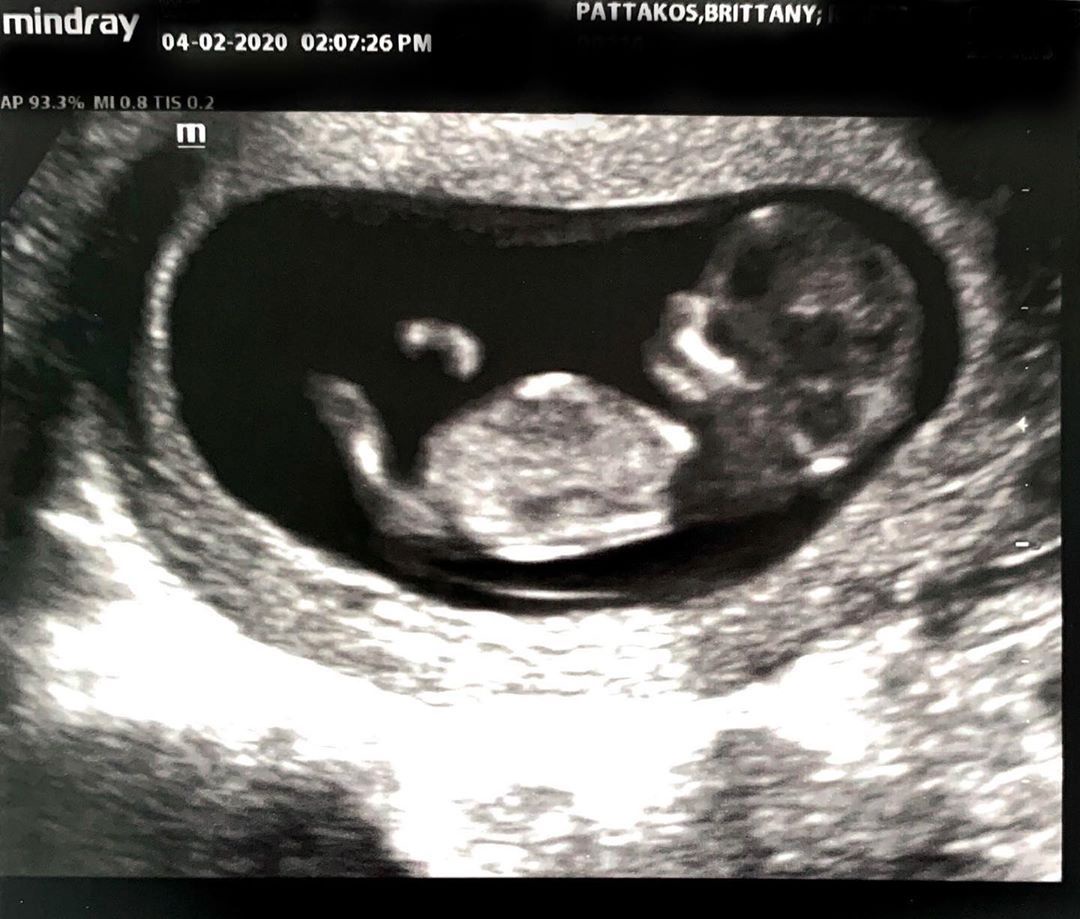

The renowned Beverly Hills plastic surgeon and star of Botched revealed the happy news in an April 15 Instagram post. Paul shared Brittany’s sonogram, showing a beautiful little bundle of joy growing in her tummy.

He ended his message with a red heart emoji. Brittany, who says she’s 13 weeks along, revealed that the baby’s sex is only going to be a surprise to Paul. She posted one of her sonograms, which show’s the little one’s hand raised up